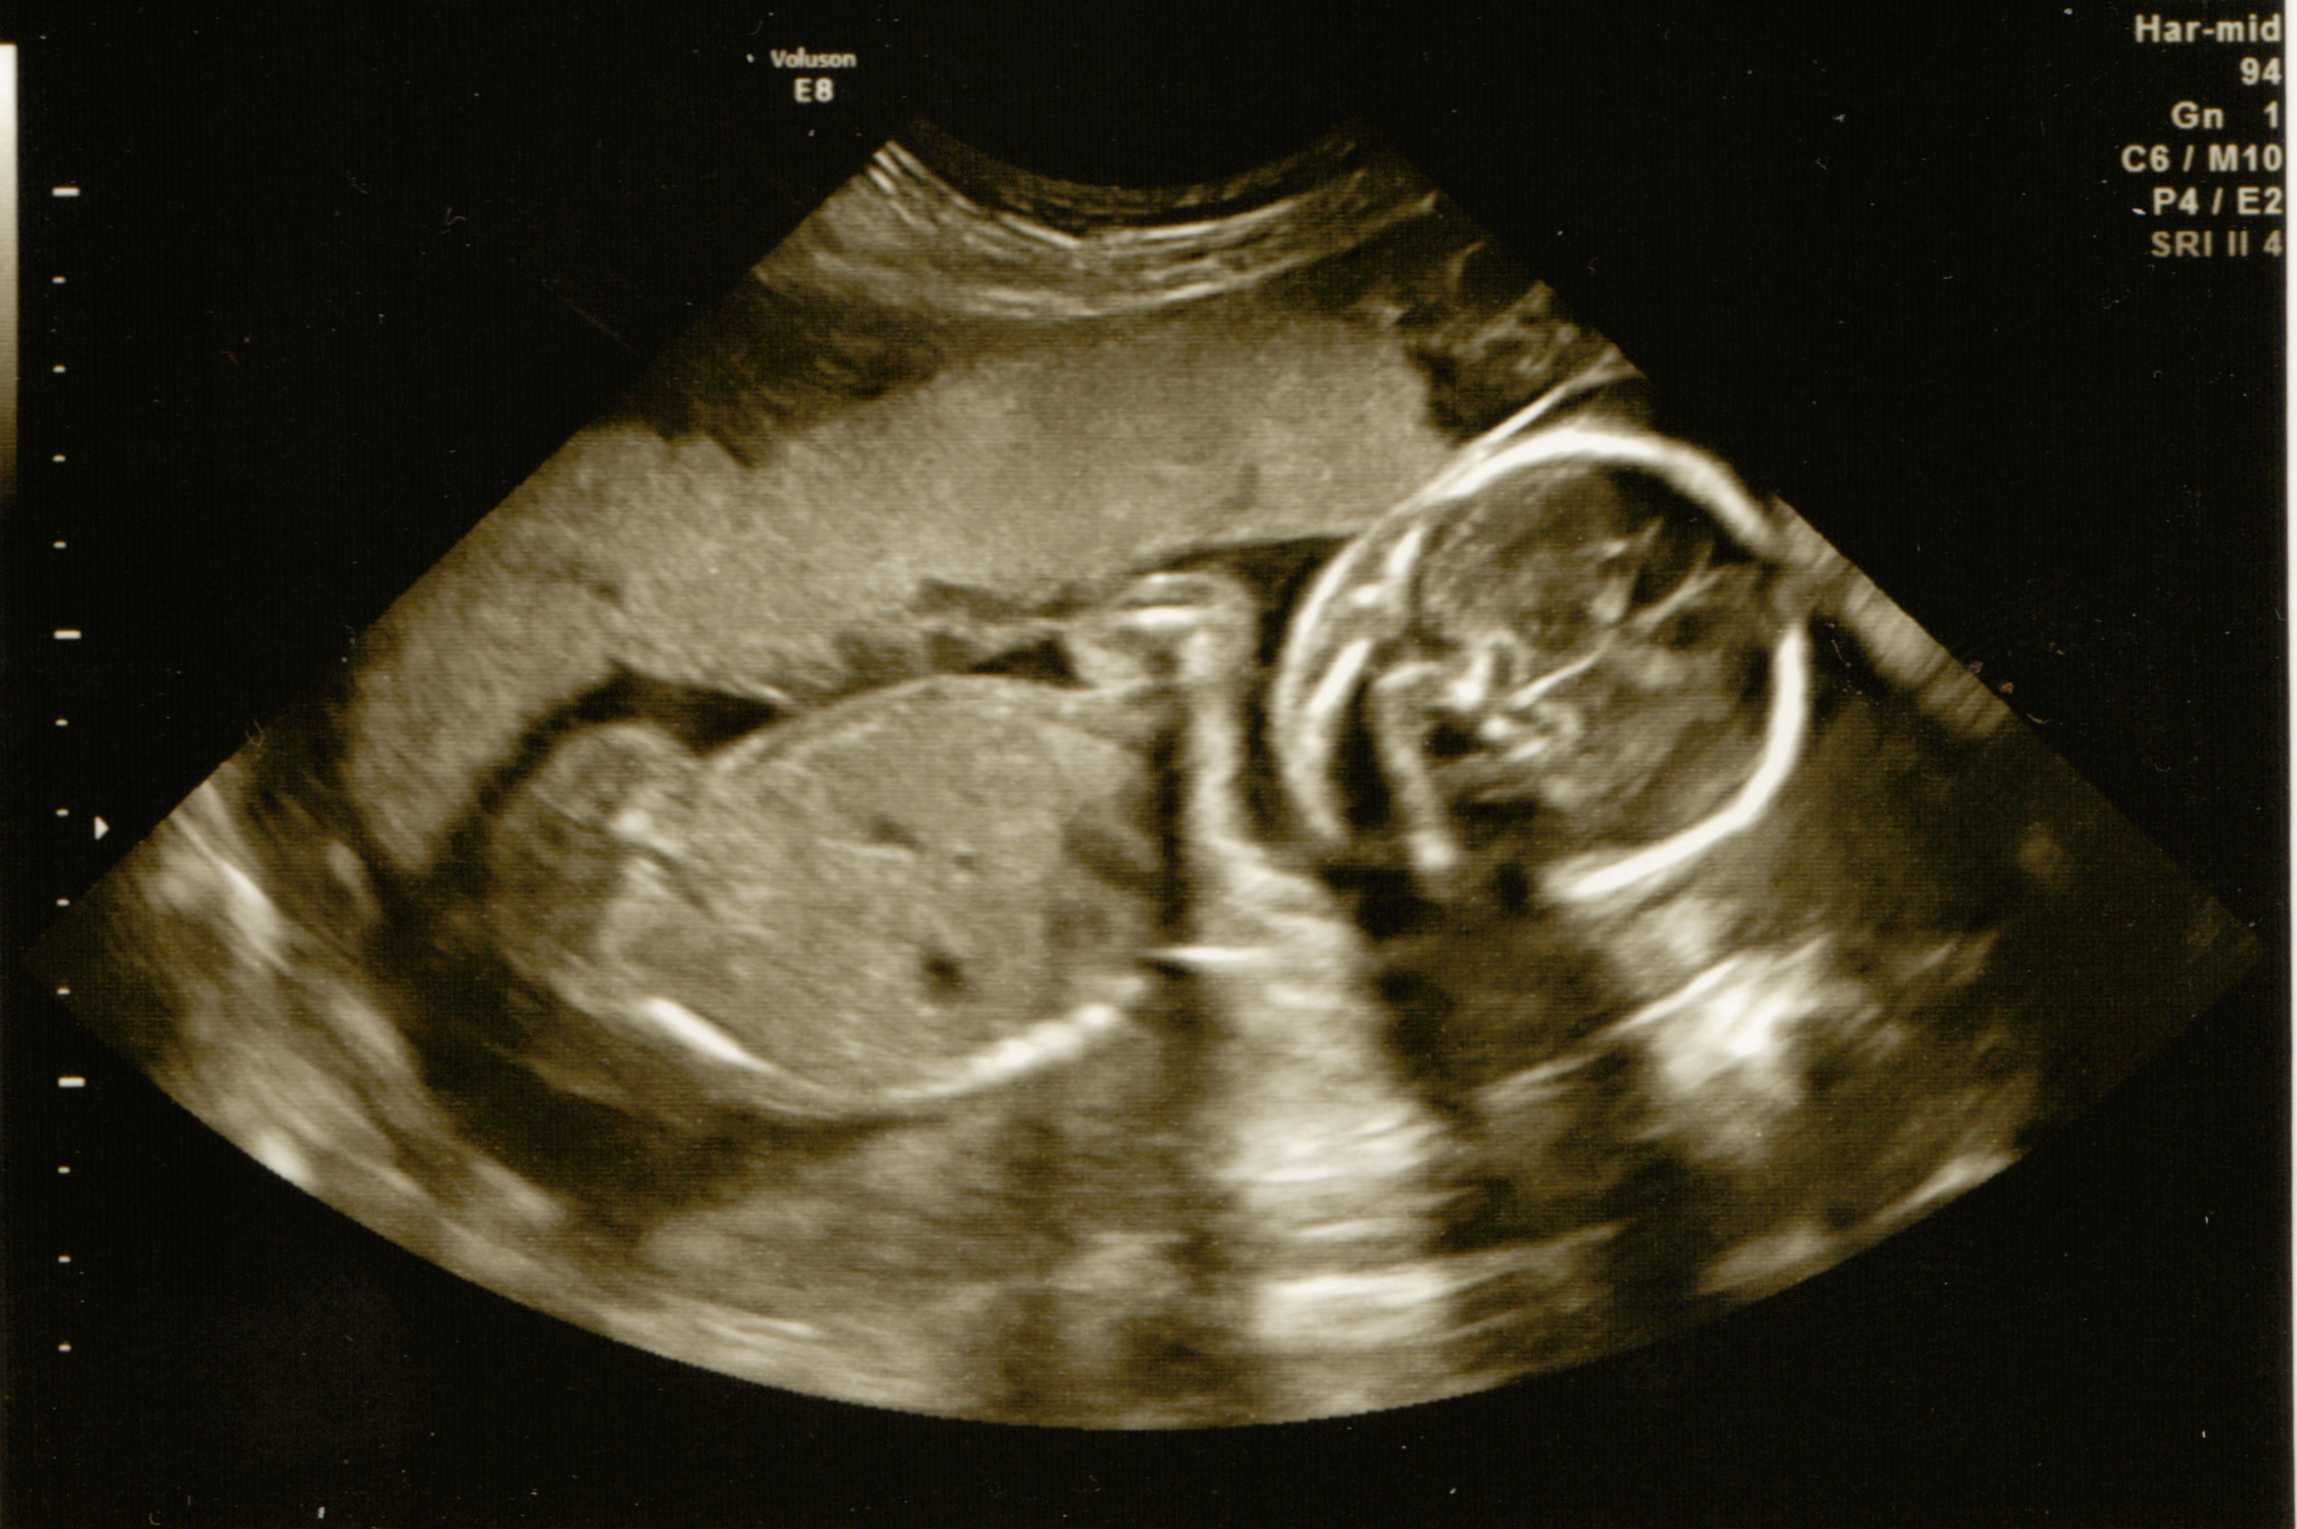

As my hospital won't tell me the sex of the baby, does anyone have any ideas? Thanks :)Attachment 1641